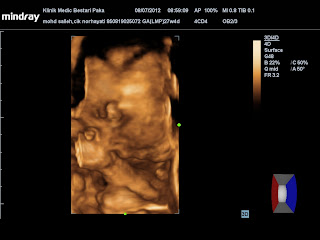

ok ari ni aku nak update pic my baby...teka boy ke gurl......

MY BABY Y TERSANGAT AKTIF

ni masa 27 minggu.....i so nervous....tak sabar nak jumpe dia di alam nyata.....my baby ni mmg cerdik bukan nak bangga tapi klu papa dia pegang atau dok bersama dia mesti dia sopan....perangai serupa papa betoi....klu dng mama je sukmo nak bergusti le nak berenang le mcm2 lg...apa2 pun aku happy dengan kedatangan my baby.....